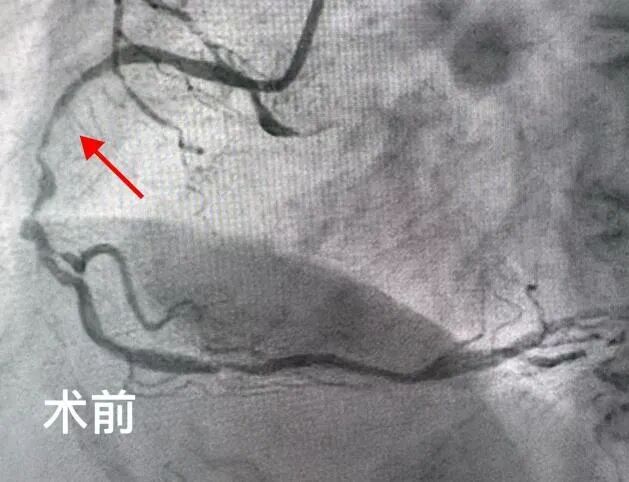

2025年5月,吉林市人民医院心内五病区收治了一位70岁的老年女性患者。该患者反复心绞痛1年,近3天症状加重。入院后,冠脉造影检查明确显示其存在严重的三支血管病变。通常情况下,冠脉搭桥手术是此类患者的首选治疗方案,但家属综合考虑患者年龄和身体状况,最终选择冠脉介入治疗。经心内五病区张金子主任团队审慎评估,决定分两次为患者实施支架植入术。

第一次手术顺利完成,在患者右冠状动脉植入两枚支架,心绞痛症状有所缓解,但仍反复发作。经过两周的精心调整,5月25日,患者再次入院接受第二次支架植入手术。然而,术后返回病区时,患者突发严重并发症——因剧烈恶心呕吐,吐出大量鲜血。由于患者既往有慢性胃炎病史,这一突发状况导致其病情急剧恶化,生命危在旦夕。 专 家 介 绍 吉林市人民医院心血管内科五病区主任 熟练处理各种疑难复杂病变,急性心梗介入治疗,慢性闭塞病变(CTO),左主干病变,分叉病变,血栓病变,口部病变,迂曲钙化病变,桥血管病变等介入治疗,熟练掌握各种分叉支架术式(crush,cullote),IABP(主动脉球囊反搏泵)辅助下高危病人介入治疗,IVUS(血管内超声),OCT(光学相关断层扫描技术)及FFR(冠脉血流储备检查)等各种设备及腔内影像学检查,为一名成熟独立术者。 以第一申请人申请市级课题一项;共发表论文11篇,其中核心期刊4篇;参与“国家级自然基金”课题1项;2018年于北部战区总医院心内科完成冠脉介入基地学员培训并获得冠脉介入资质证书;2020年于北部战区总医院心内科完成心血管专科医师培训,同年取得中国医师协会颁发的专科医师规范化培训合格证书。2022年于北部战区总医院心内科完成培训并获得结构性心脏介入资质证书。 吉林市昌邑区人大代表;吉林省老年心血管预防康复委员;吉林省中西医结合学会第一届心衰防治与康复专业委员会委员;2022年昌邑区十九届人民代表大会代表;2022年度吉林市昌邑区优秀人大代表;2022年吉林市统战最美统战人新阶层创新之星;2023年度吉林市昌邑区优秀人大代表。